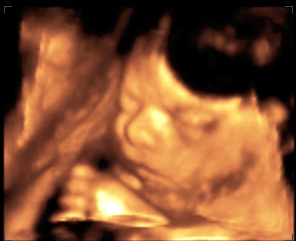

Akkor a képek (hétfői -31hét 6nap)

Kép Kép

KépKép

Azta Moncsi, szép nagy pocakod van :D Hogy bírod???Még 8 hét vissza van, pihenj amennyit csak tudsz...